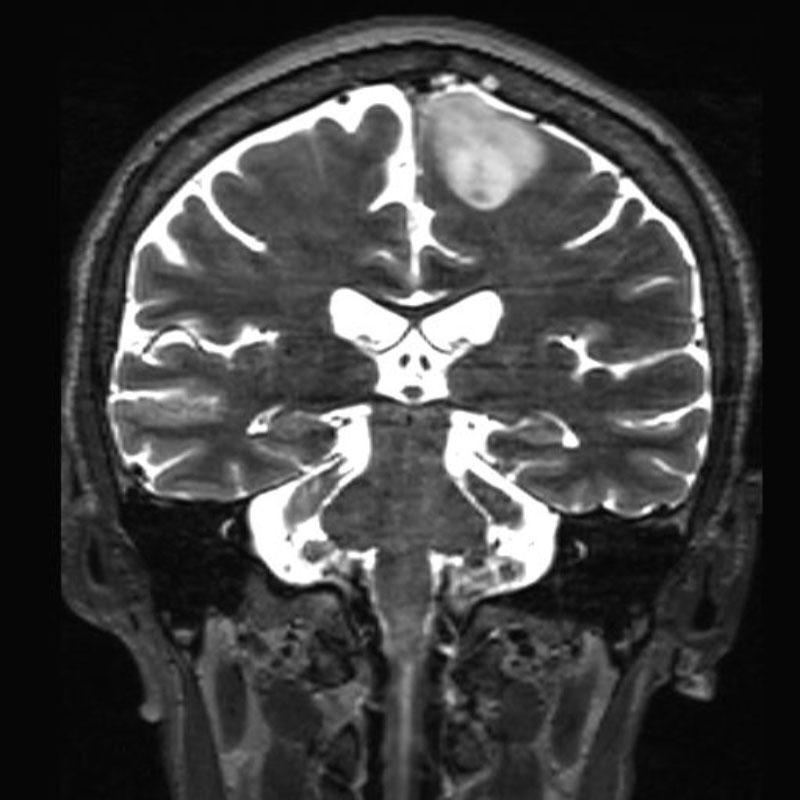

手術前1

手術前2